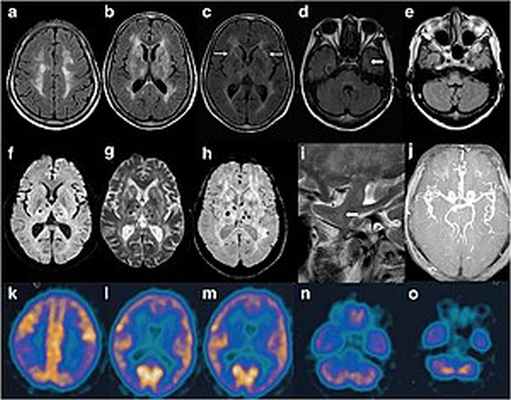

| Изображение черепа пациента с FFI. На МРТ наблюдаются аномальные сигналы в двусторонней лобно-теменной подкорковой области. МРА показала меньшие дистальные ветви церебральных артерий. | |

Само по себе присутствие прионов вызывает снижение использования глюкозы таламусом и умеренный гипометаболизм поясной коры головного мозга. Степень этого симптома варьируется между двумя вариациями заболевания, это те, которые представляют собой гомозиготы по метионину по кодону 129, а гетерозиготы по метионину / валину являются наиболее тяжелыми в более позднем варианте. Учитывая взаимосвязь между участием таламуса в регулировании сна и бдительности, можно установить причинную связь, которая часто упоминается как причина.

Несмотря на чрезвычайную редкость фатальной семейной инсомнии, заподозрить именно это заболевание практикующему врачу позволили бы клиническая специфичность, абсолютная терапевтическая резистентность и быстрое прогрессирование психоневрологической симптоматики по сценарию «снежного кома». Следует, однако, дифференцировать данную прионопатию от симптоматически сходных агрипнических и инсомнических синдромов. Наибольшей информативностью в этом плане обладает медико-генетическое исследование (изучение семейного анамнеза), нейрофизиологическая диагностика процессов сна и бодрствования, а также ПЭТ, МРТ и другие визуализирующие технологии, позволяющие выявить характерные органические изменения в структурах головного мозга.